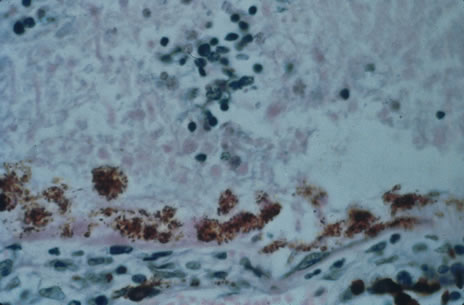

Any cell type may be infected, appearing larger than normal (cytomegalic) and demonstrating eosinophilic intranuclear “owl's eye” and smaller intracytoplasmic viral inclusion bodies, which are better seen with Giemsa or Papanicolaou's stains (Fig. 8). Histologic examination of tissue specimens, including bronchoalveolar lavage fluid and urine, may be useful for diagnosis.